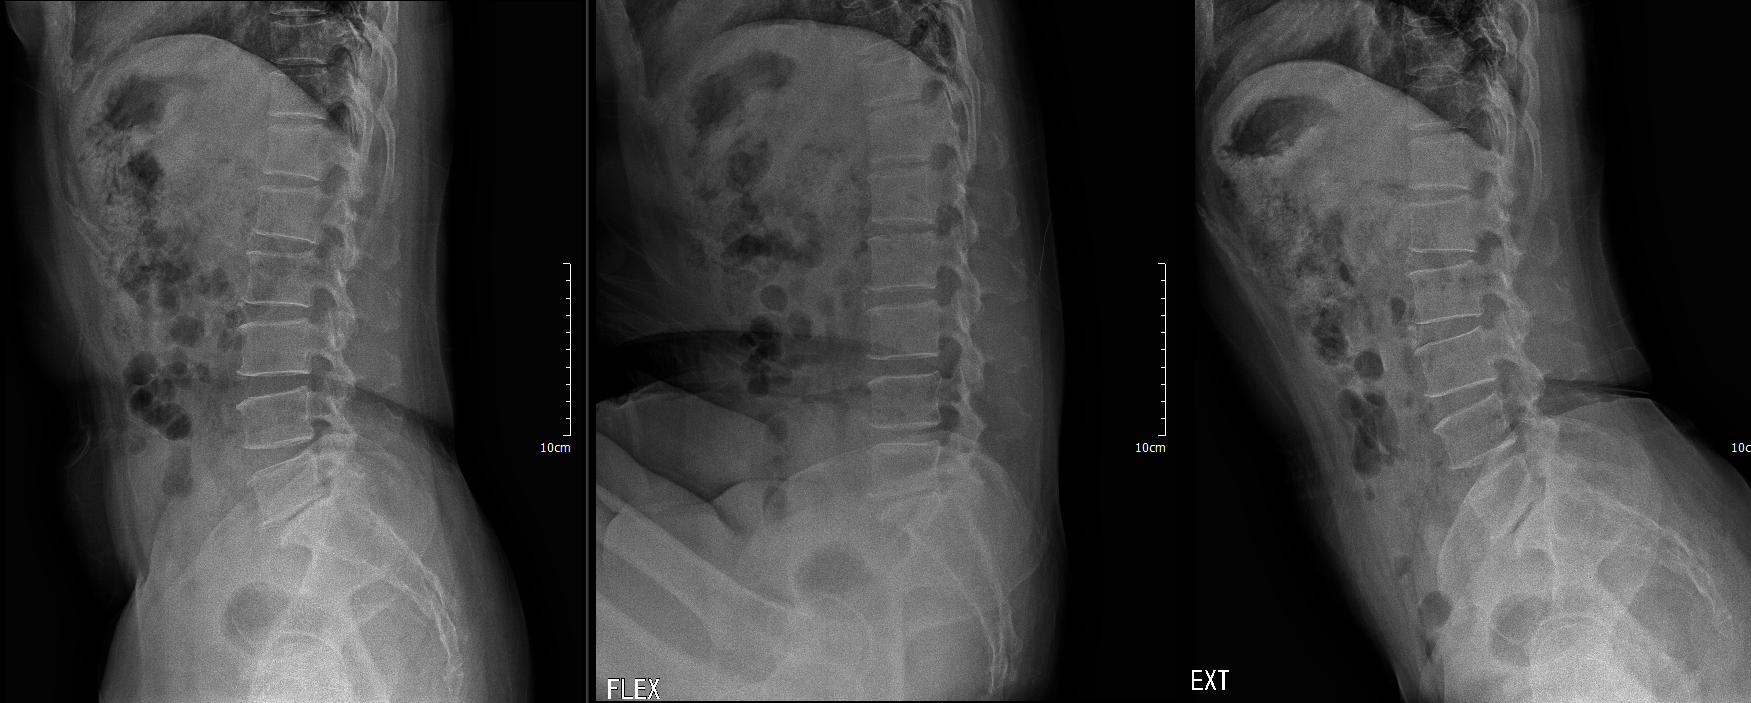

타병원에서 nucleoplasty 이후

Postop MRI

MRI 에서 dura tear 의심소견이 있어 판독까지 받아보았다.

역시나 dural defect...